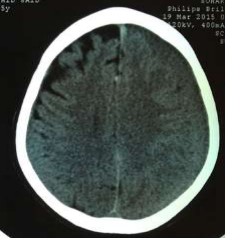

Fig 1,2,3,4,5,6,7,8,9,10,11,12,13,14,15

Thirty eight out of Eighty-two patients were treated conservatively and were studied (25 men; 13 females, mean age, 64.8 years). The average thickness of the hematoma was 18 mm, the mean midline shift was 4.7 mm, and the average attenuation value of bleed on computed tomography scan was 33.5. Thirty-eight were treated successfully with steroid treatment, whereas 44 patients required surgery. The female gender, less midline shift, less density (Hounsfield units) was noted to be associated with successful medical treatment. We propose a grading based on the total score given to the midline shift and density.

Figure 9

Figure 10